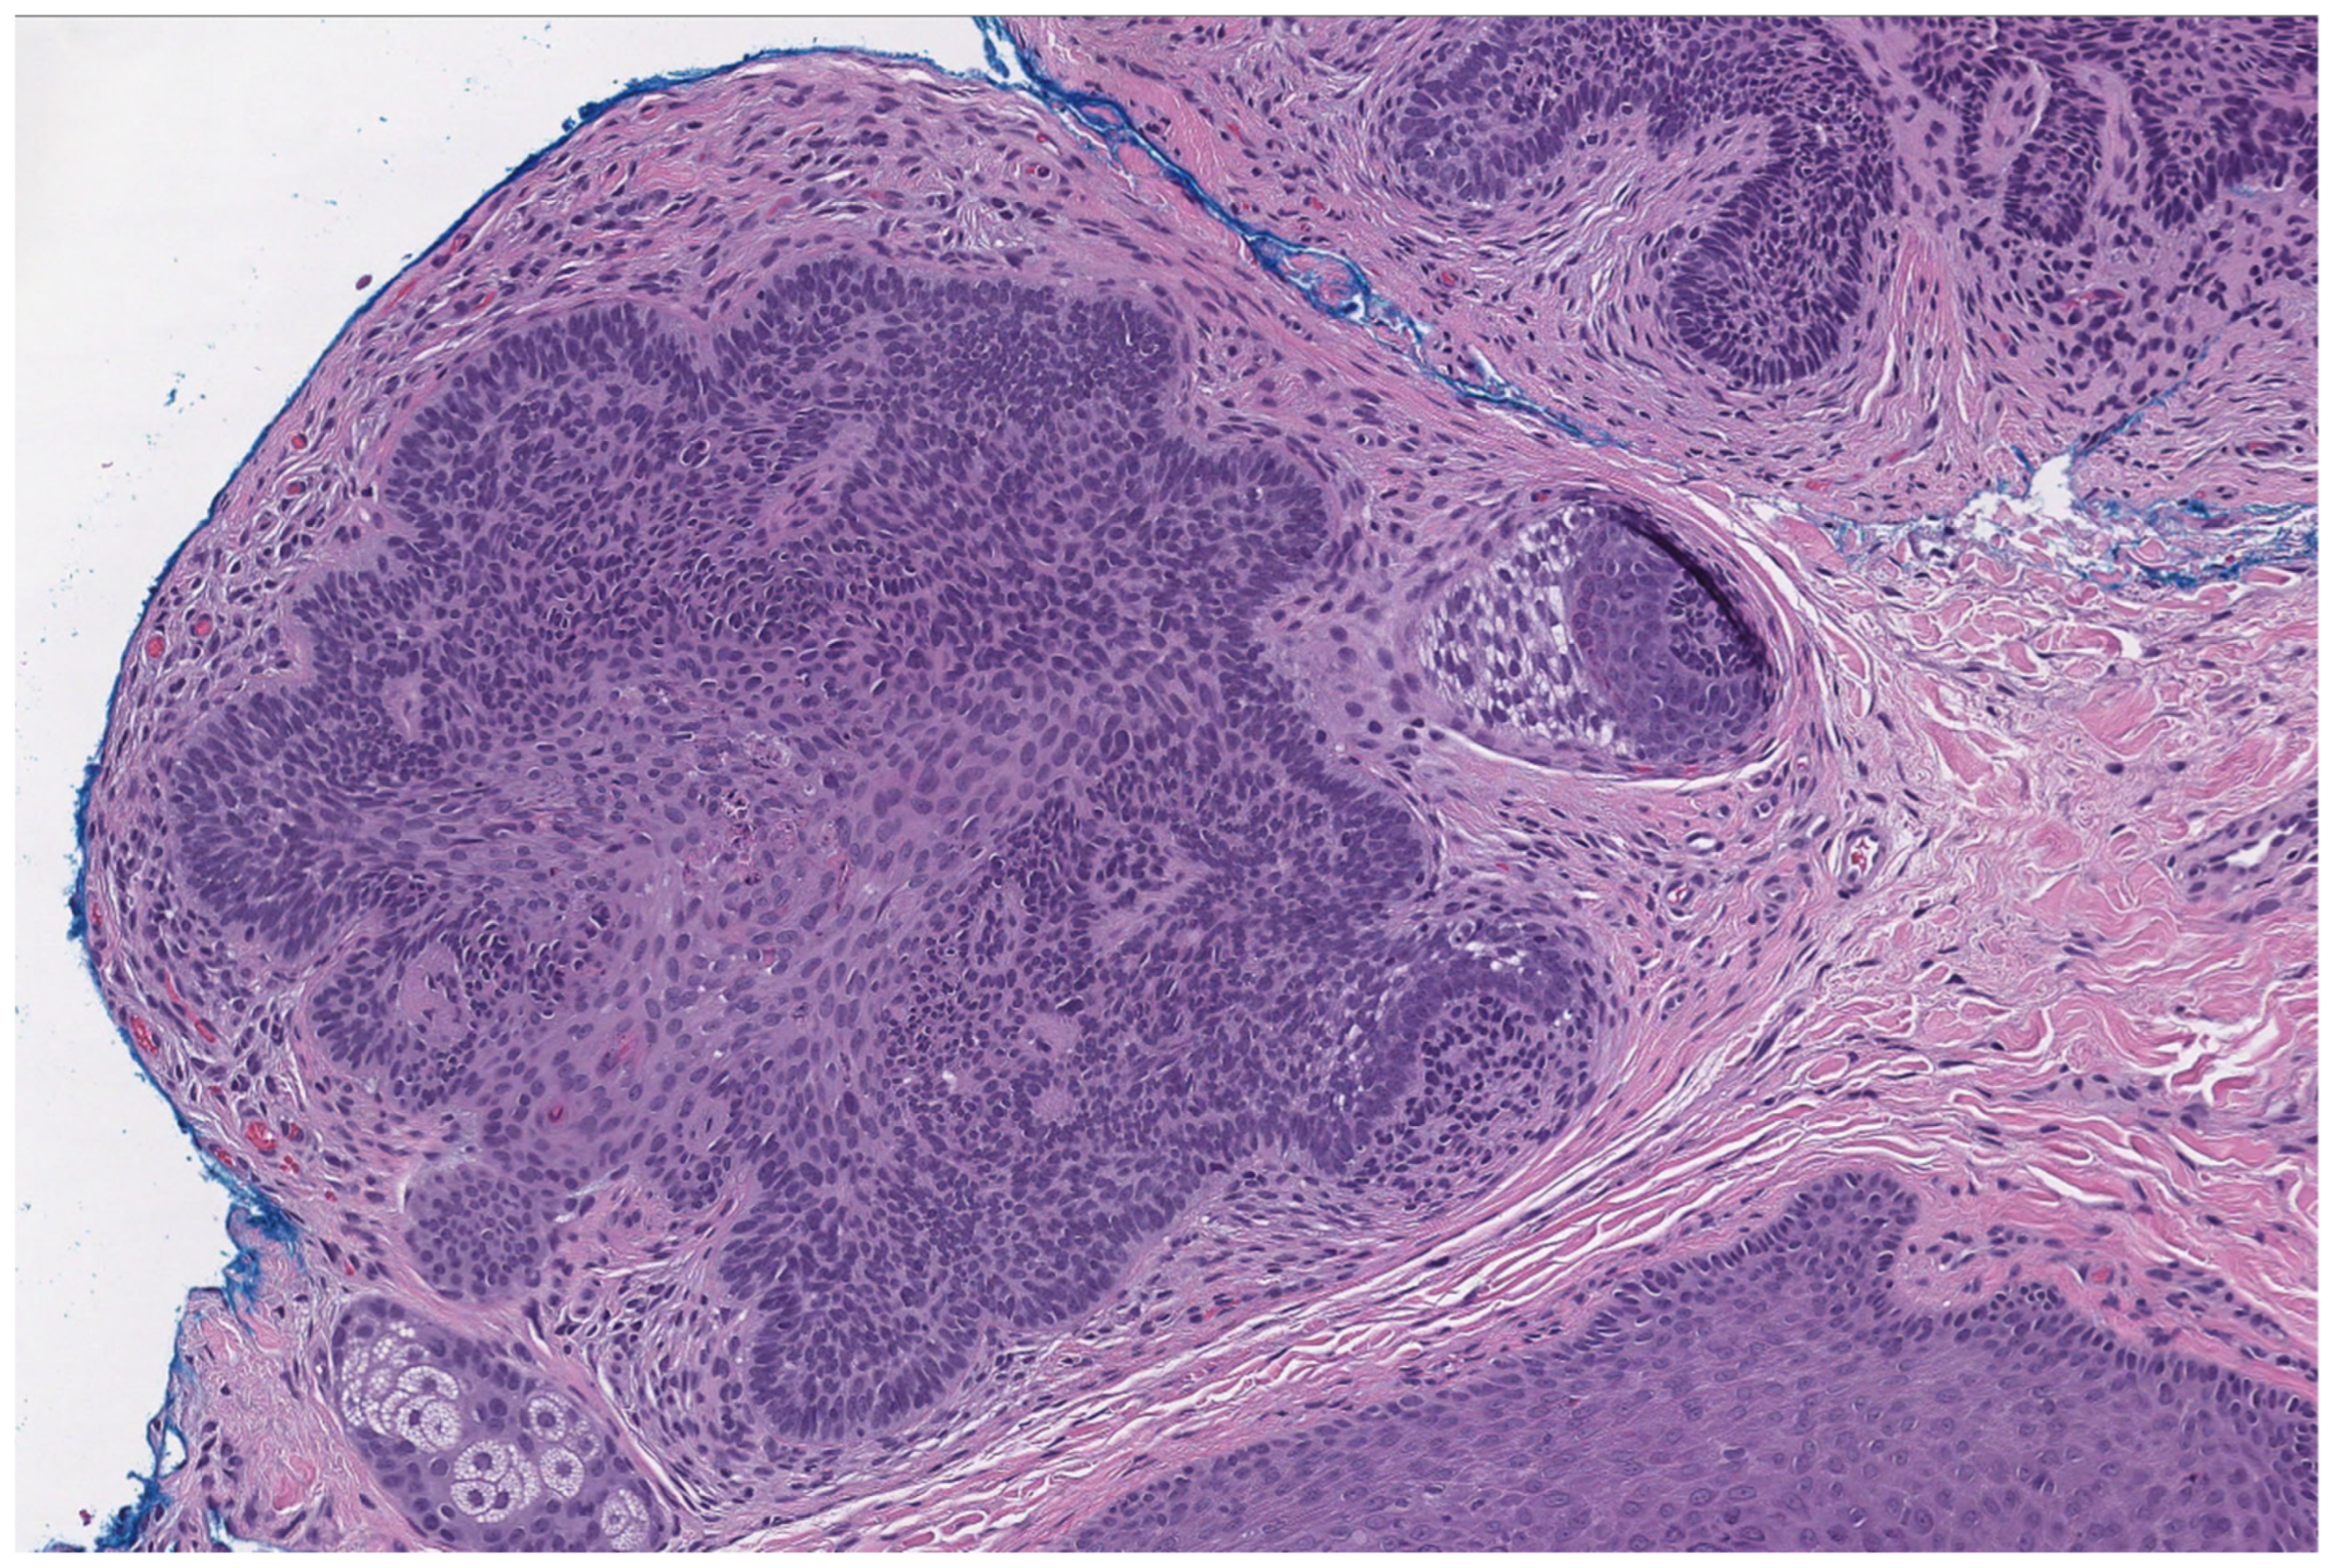

2.2. Tricholemmoma